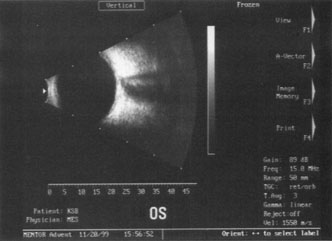

A mature cataract precludes visualization of the fundus. A B-scan ultrasonographic examination provides a real-time, two-dimensional (2D), cross-sectional image of the globe along the marked axis of the probe (Fig. 3). Cataracts are more common in patients with chronic retinal detachment, prior trauma, or intraocular tumors; therefore, a B-scan study is helpful in excluding structural posterior segment pathology before surgery on a mature cataract. Although a negative result to B-scan evaluation is reassuring, the surgeon should remember that it does not predict postoperative visual outcome. The B-scan can be thought of as a picture of Cincinnati from an airplane; the office buildings may all be standing, but you cannot tell whether the people in them are working.

Fig. 3. This B-scan ultrasound shows a normal looking posterior pole, without retinal detachment or intraocular mass. The vitreous cavity is echo lucent.